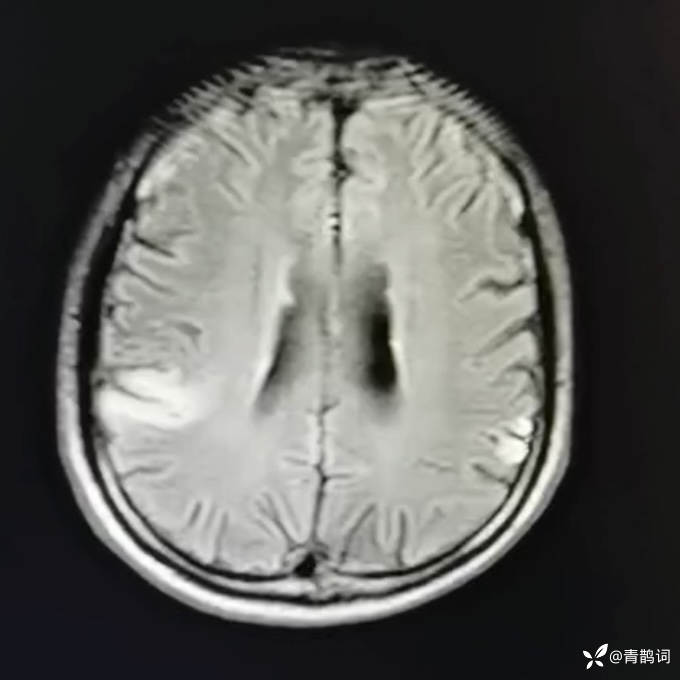

乐痴于医等 2人推荐简要病史:42岁男性,记忆力下降及听力下降一年余。既往体健,否认前驱感染病史。否认家族史。三个月前就诊于当地医院,自述腰穿脑脊液乳酸增高。现就诊于我院,查体记忆力下降,计算力下降,定时定向差,吟诗样语言。完善磁共振如下:

T2: